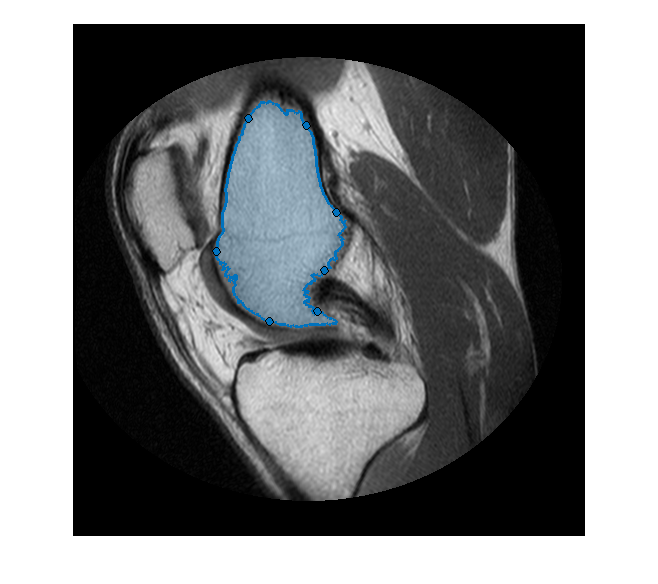

В этом примере показано, как создать простой инструмент, чтобы отредактировать форму ROI от руки с помощью другого объекта ROI. По умолчанию, Объекты ROI включают waypoints, который можно перетащить, чтобы отрегулировать форму ROI. Можно также добавить waypoints в интерактивном режиме в любую часть контура.Freehand

Другим способом отредактировать форму ROI от руки, предлагаемых многими популярными программами преобразования изображения, является инструмент 'кисти' или 'средство стирания'. Этот пример реализует один из этих инструментов, с помощью другого объекта ROI отредактировать ROI от руки.

Создайте ROI От руки, который следует за формой маски сегментации. Для получения дополнительной информации об этом процессе смотрите Использование ROI От руки, чтобы Совершенствовать Маски Сегментации.

Создайте ROI от руки в сегментированной маске.

hf = drawfreehand('Position', pos);

Эта анимация показывает добавление, и удалите операцию редактирования.